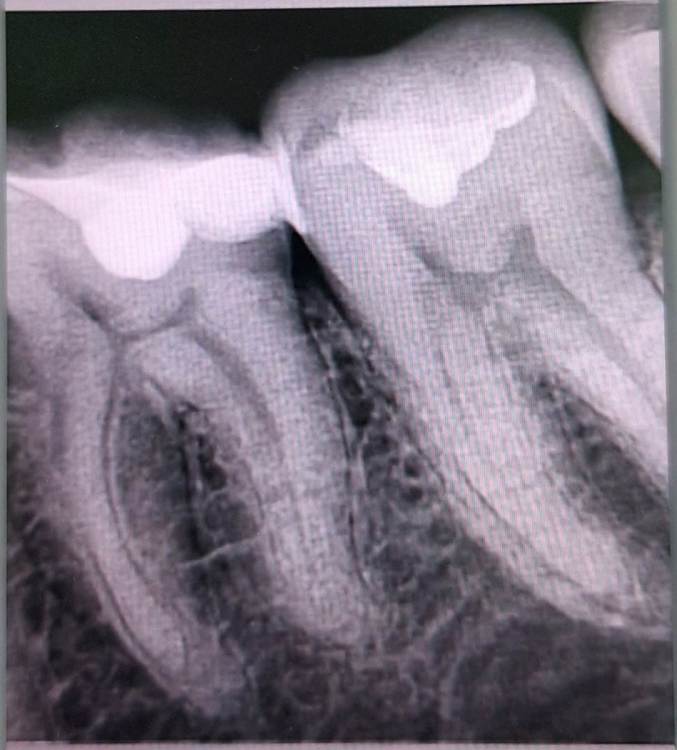

fcb99 Опубликовано 19 декабря, 2023 Поделиться Опубликовано 19 декабря, 2023 Здравствуйте. Месяц назад 18.11 переделывали нижнюю шестёрку. Старая пломба (световая 17 г.) почему-то слегка провалилась или стерлась и стало больно при попадании пищи. Поставили новую. С тех пор реагирует на горячее/ холодное и больно при попадании твёрдой пищи/ надавливании. Врач сказал придется удалять нерв. А хочется сохранить. Есть ли смысл идти в другую клинику, делать кт и тд. Или это стандартная ситуация и решение? Спасибо. (На рентгене слева) Ссылка на комментарий

Carioznik Опубликовано 19 декабря, 2023 Поделиться Опубликовано 19 декабря, 2023 8 часов назад, fcb99 сказал: Врач сказал придется удалять нерв Я бы не торопился с удалением "нерва" (исходя из приведенных Вами данных). Ссылка на комментарий